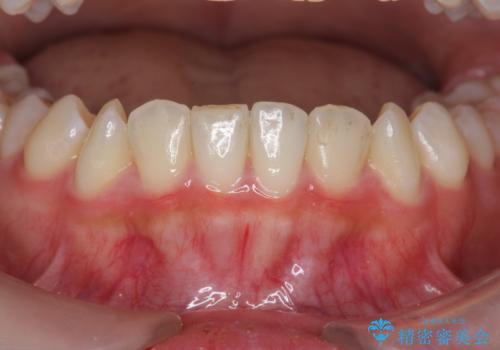

インビザラインライトで行う短期マウスピース矯正治療

- 前歯のガタつきを並べたいたいと、矯正治療を希望され来院されました。

とにかく短期間で前歯だけの治療を行いという希望が強く、全体矯正と前歯だけの部分矯正の仕上がりのイメージを確認したのち14枚のマウスピースで前歯のみの矯正治療を行っていくこととしました。

インビザラインライトは軽度なガタつきや傾斜の改善に用いられる全14枚のマウスピース矯正です。

短期間で治療の終了が見込めるだけでなく、料金もインビザラインフルに比べリーズナブルです。